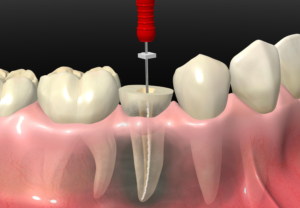

Endodoncia Uniradicular

Tratamiento en dientes de una sola raíz que elimina la infección interna, quita el dolor y permite conservar el diente por más tiempo.